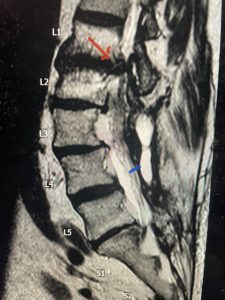

Epidural lipomatosis is a relatively rare condition where normally present fat in the epidural space is hypertrophied and can cause severe thecal sac compression. It is generally deposited more in the lateral and dorsal epidural space. This can be caused by long term steroid use and obesity, but also can be idiopathic. He had done well until more recently had developed low back pain with bilateral thigh pain and numbness. He had difficulty walking because of the pain. A new MRI (Fig 5) revealed that he had developed severe degeneration of the L1-2 segment above his prior decompression and fusion with a large extruded disc/osteophyte, right greater than left with severe thecal sac compression. He also had some residual T12-L3 residual epidural lipomatosis.

He had failed conservative treatment consisting of neurontin, physical therapy and epidural injections. He underwent revision laminectomy T12-L3 to decompress and explore prior fusion. He did have significant epidural fat encountered particularly at L1-2. The fat in epidural lipomatosis has a much more firm, globular texture. It takes a while to search within the fat, gently dissecting with a Penfield 4, to finally find the thecal sac! We encountered a large subligamentous extruded fragment lateral to the thecal sac on the right above the take off of the L2 nerve root. We removed any more residual fat at the L2-3 level and T12-L1 and decompressed the sac well. On exploration of the prior fusion it was fairly solid, but had some gaps at L2-3 fusion mass. Therefore we added a T12-L3 in situ fusion to augment those gaps and because we were at the thoracolumbar junction we extended fusion to T12. Post operatively he had relief of his leg pain.

(Figs 5a): Sagittal (a) and axial (b) T2-weighted lumbar MRI demonstrating status post lumbar decompression and insitu fusion L2-5 now well decompressed (blue dash) with development of new (red arrow) severe stenosis and with superimposed right L1-2 disc herniation (blue arrow)

(Figs 5b)